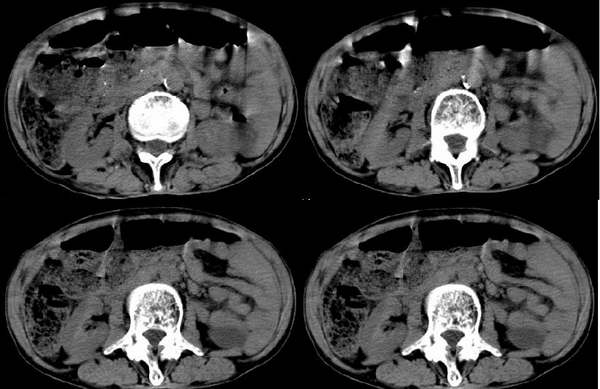

患者男,70岁,前几天外伤后摄片腰椎有压缩性骨折,今天上腹部疼痛大概半天,未大便,患者情况较差,透视下膈下未见明显游离气体。请大家会诊.

主要想了解有无内脏与消化道破裂

脏器破裂好像没有,但有肠梗阻征像。建议立位腹部平片(注意有无液气平)

好象结肠内粪便及气体较多,其它不好说。

肠道内容物较多伴积气,似有肠梗阻征象,腹部脏器未见明显异常。你要在ct片上看有无肠道穿孔和肠梗阻,请用类肺窗式的窗宽窗位观察。

脏器破裂好像没有,但肠道内容物较多伴积气有肠梗阻征像,未大便,是否因年龄大外伤引起肠功能紊乱有关

结合外伤史,考虑麻痹性肠梗阻.

有腰椎压缩性骨折的患者多伴有肠腔积气.

肝右叶后段一类圆形低密度灶,肝囊肿或小血管瘤,胃及腹部肠管明显扩张、积气、肠内容物也较多,外伤后肠功能紊乱,肠梗阻。

肠腔粪便较多,考虑肠梗阻,未见明显脏器破裂

升结肠伸入肝肾之间与膈相贴,右肾位置较低,其它未见异常。考虑间位结肠。至于有无急腹症征象,不太明显,窗宽太窄。

肝外缘可见条带样低密度影,测量一下ct值。以除外气腹。